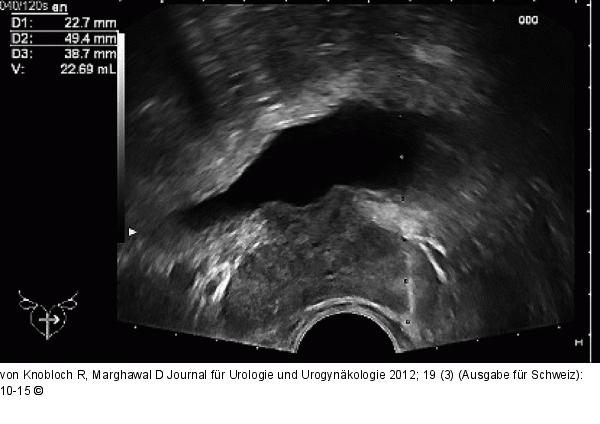

Abbildung 2: Prostatabiopsie Ultraschallbild während der Biopsie der Prostata mit Darstellung des Organs in der Transversalebene |

Ultraschallbild während der Biopsie der Prostata mit Darstellung des Organs in der Transversalebene |